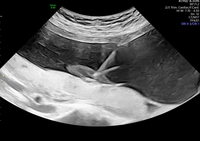

Nabelschnurpunktion – Cordozentese und intrauterine Transfusion

Manche Situationen erfordern eine direkte Untersuchung des kindlichen Bluts, z. B. bei bestimmten kindlichen Erkrankungen oder bei aufwendigen genetischen Untersuchungen. Hierdurch kann die Untersuchungszeit im genetischen Labor deutlich verkürzt werden. Die Punktion wird meistens ambulant durchgeführt. Ähnlich wie bei einer Fruchtwasseruntersuchung wird eine dünne Nadel über die Bauchdecke in die Fruchthöhle eingeführt und dann unter ständigen Ultraschallkontrolle aus der Nabelschnur etwas Blut abgenommen. Auf demselben Weg kann auch eine Bluttransfusion erfolgen, wenn der Fetus an einer Blutarmut leidet, z. B. bei Rhesusunverträglichkeit der Mutter oder Ringelrötelinfektionen. Das Blut stammt dabei von freiwilligen Spendern und ist in der Blutbank genauestens auf Infektionserreger und Verträglichkeit getestet worden.

Fetalblutabnahme